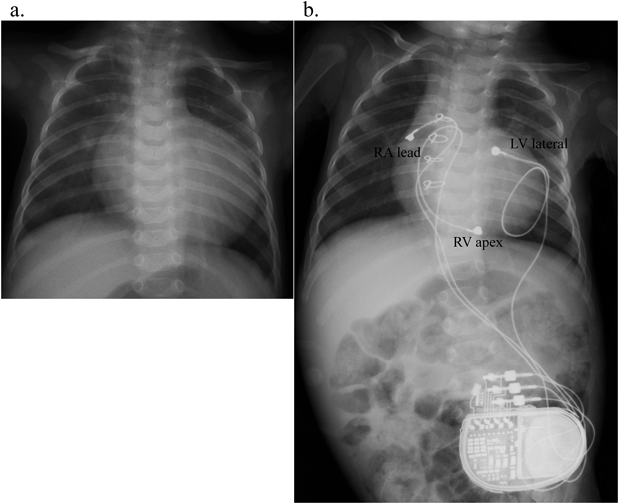

Fig. 1 Chest X-ray before and after CRT-P implantation

a. CXR before CRT-P implantation. b. CXR 1 month after CRT-P implantation. Three unipolar steroid eluting suture-on type lead (4965 Medtronic) were placed on RA, RV apex and LV lateral wall by left thoracotomy and median sternotomy.

成人の症例では左室リードは多極リードが使用できるようになり,植え込み後に任意のペーシング部位を選択できるようになった.一方,小児の場合は開胸でのリード植え込みとなるため,任意の場所に留置することができる反面,至適ペーシング部位の決定はCRTのoutcomeを左右する重要な問題である.左室の心室内非同期を改善させることが目的であることから,右室は流出路から心室中隔へ伝導させるか,心尖部から心室中隔へ伝導させるかどちらかということになる.現時点ではspeckle trackingでmechanicalなdelayを評価して再遅延部位を指標に左室リードを逢着するのがいいと考える.Fig. 3bに示す例ではseptal to posterior wall motion delay(SPWMD)で見ると,中隔と左室後壁にmechanicalな収縮時相のズレが認められる.このmechanicalな収縮時相のズレを局所の非同期性だけでなく,心室全体の動きについて収縮期の時相のずれを見ることができるのがspeckle tracking法(Movie 1)である.Fig. 1a, bにCRT-Pシステムの植え込み前後のレントゲンを示す.右房,右室,左室の3カ所にリードを逢着するため,BipolarリードよりUnipolarリードを選択することも心臓の絞扼性障害を避けるためには有効な手段である.